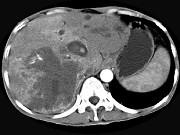

问题 男,44岁,右上腹痛半年,腹部未触及包块,轻度黄疸,AFP阴性,CT检查如图,最可能的诊断为()

选项 A.原发性肝癌 B.胆管细胞癌 C.肝囊肿 D.肝脓肿 E.肝血管瘤

答案 B